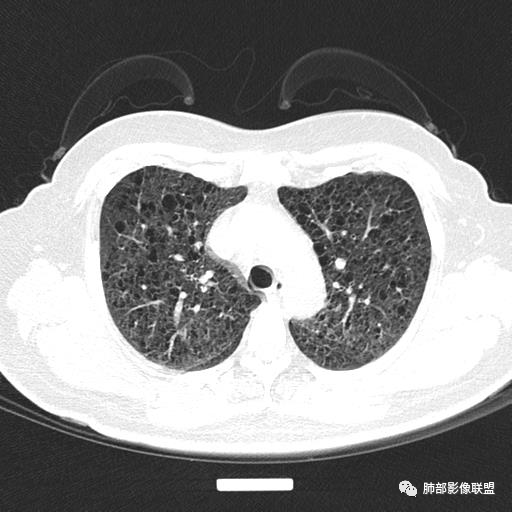

中年女性,不吸烟

双肺弥漫囊腔,累及肋膈角,囊腔形态相对规则单一。

CT平扫示双肺弥漫分布大小不等囊状薄壁透光区,无内、中、外带分布差异,间质稍示增厚。拟LAM

中年女性育龄期妇女,咳嗽气喘,无吸烟史,有苯吸入史。影像:双肺弥漫均匀小囊腔,无明显分布优势,囊腔形态欠规则,壁薄,部分囊腔边缘血管征,伴双肺弥漫磨玻璃影,无结节,考虑lam,鉴别苯中毒肺损伤,囊腔多有分布优势,小叶中心分布为主,形态规整等

女,46,活动性气喘1年。苯吸入史半年。胸部CT:两肺弥漫囊腔,上至肺尖,下至肋膈角,形态类似小囊腔。考虑:LAM,鉴别LIP,BHD,PLCH等。

双肺弥漫大小不一薄壁含气囊腔,囊间肺组织正常,正常肺背景,肺尖肺底受累;青年女性,气喘,支持LAM

CT表现:双肺弥漫大小不等的薄壁囊腔,囊壁<2mm,外形规则,血管影多位于囊腔周围,囊腔之间肺组织正常,随着疾病进展到晚期,囊腔变大、增多,不可胜数,囊腔可融合成较大的囊,与肺气肿相似,形成间质性肺纤维化。部分病例可出现结节影。